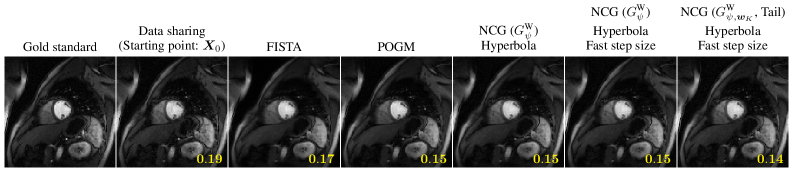

using unitary invariance of the Frobenius norm. Then (95) is equivalent to R𝜓,𝒘\nabla R_{\mathop{{}\psi}\nolimits,\bm{w}} being LL-Lipschitz where L=𝒘ωψ(0)L=\left\|\bm{w}\right\|_{\infty}\mathop{{}\omega_{\psi}\left(0\right)}\nolimits [beck:17:fom, Thm. 5.8] when considering the inner product in (14).